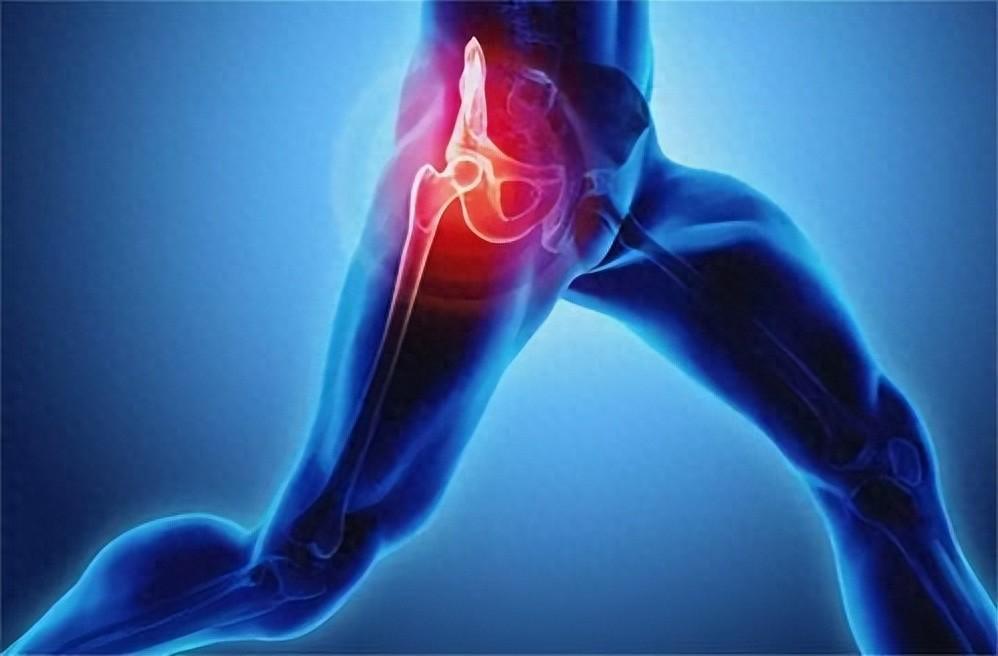

2.對骨骼的影響:偏酸的體液刺激副甲狀腺,使副甲狀腺素分泌增多,骨骼釋放到血液中的鈣增多,鈣雖然可以中和血液中的酸,但這樣長期「借」鈣的結果,會導致骨質疏鬆、骨質增生、骨骼變形及損傷等。